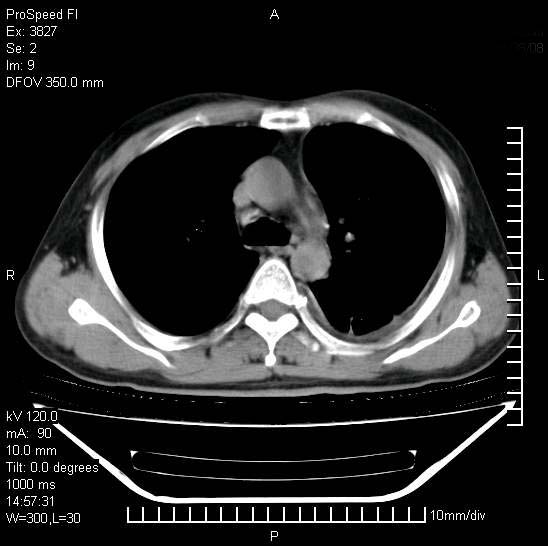

男性,一月前出现右侧肋区疼痛,较剧烈,干咳,无发热,自诉使用抗炎药后缓解,几天前又出现左侧剧烈疼痛,

发热,体温38。9,今天ct,考虑左侧包裹性脓胸,胸腔积液,右上中肺小斑片影,结核/炎症?胸水未见恶性细胞。

支持:脓胸!并双肺继发性肺结核!

左侧肺脓疡,化脓性胸膜炎(脓胸),不支持结核诊断,建议继续抗感染治疗

支持左侧肺脓肿并脓胸,肺内炎症,建议继续抗炎治疗后复查。

脓胸没问题,肺内还可见感染灶,感觉不像是结核性病变.